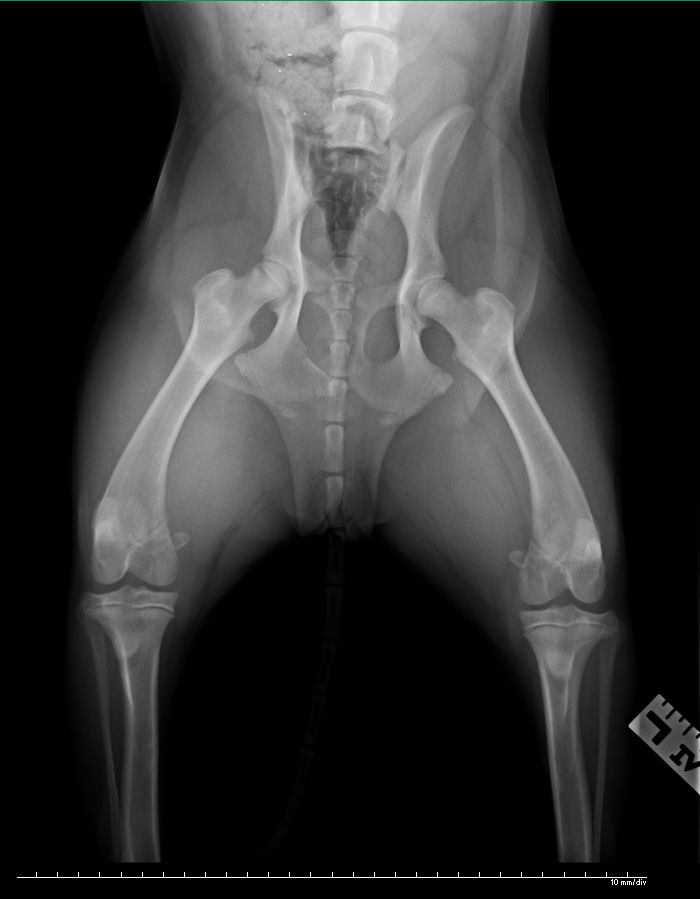

I called the emergency vet clinic on the way and they took her to the back immediately upon arrival. I was asked to fill out paperwork, which I did, scrawling “I have financial limitations.” across the top. After awhile, the vet who had examined her spoke to me about his findings. The injuries did not appear to be grave and he explained that despite the fact that I was being handed an $800 estimate for care that would be ideal, much of it was precautionary in nature. I was given the option to go through the estimate item by item, picking out the services I could afford. He strongly recommended at least one x-ray. I picked out $200 worth of services, including an x-ray. This is that x-ray:

The dog’s pelvis is fractured in 2 places but they will heal on their own, with approximately 6 weeks of cage rest. The vet said, “She got lucky.” I was never so happy to hear 3 words. The vet told me the story of the Good Samaritan from the Bible and thanked me for not leaving the dog in the lobby, which he said happens regularly. He gave me $50 off the bill. They sent us home with pain pills and home care instructions.

Actually, I think Jade is younger the 9 months. Her growth plates are still wide open. Which means she has an even better chance of healing because her bones are so actively growing.

Thanks for letting me know. The vet did point out the growth plates on the x-ray to me. So interesting as I’ve never seen them before. I thought growth plates normally close about 12 months of age but have no idea what the width of hers suggests age-wise. If you have an age guess for Jade based upon what you see in the film, I’d be happy to hear it.